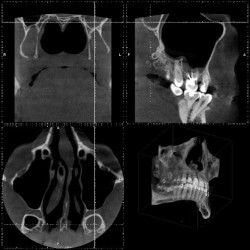

- рентгенография или КТ околоносовых пазух;